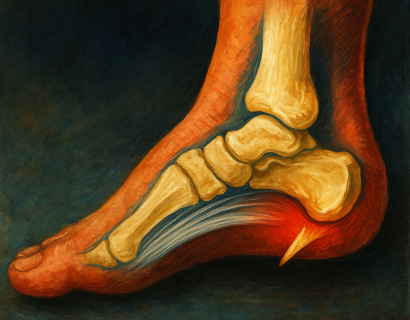

Ахиллово сухожилие — самое мощное и прочное сухожилие в организме человека. Оно соединяет икроножные мышцы с пяточной костью и играет ключевую роль в способности ходить, бегать, прыгать и даже просто вставать на носки.

Пяточная шпора — это не просто дискомфорт в стопе, а частая причина хронической боли, ограничений в повседневной активности и снижения качества жизни.